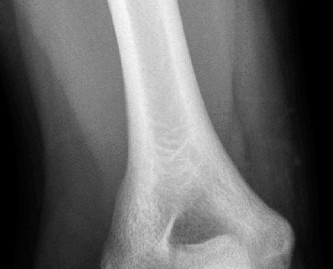

Physically examine a patient for classic posterolateral instability? Understand the potential treatment options? CASE 37 A 53-year-old, left-hand-dominant male presents to your office for evaluation regarding his elbow pain. He states that for the past 5 years he has had pain in his left elbow. It seems to be worsening over the past 6 months. He states he works as a mechanic and the pain is limiting the amount of time he can spend working. He takes anti-inflammatories with some relief. His images are shown (Figs. 2–97 and 2–98).

Figure 2–97

Figure 2–98

The correct answer is (A). Pain when carrying heavy objects with the elbow in extension is a classic presentation for patients with early disease. They also have

motion loss less than 15 degrees and respond well to conservative treatments. Patients with intermediate disease have moderate pain at the ends of motion, often have loss of extension >30 degrees and have ulnar nerve symptoms. Patients with end-stage OA have pain in the mid-arc of motion, have failed conservative treatment and have motion loss greater than 30 degrees.